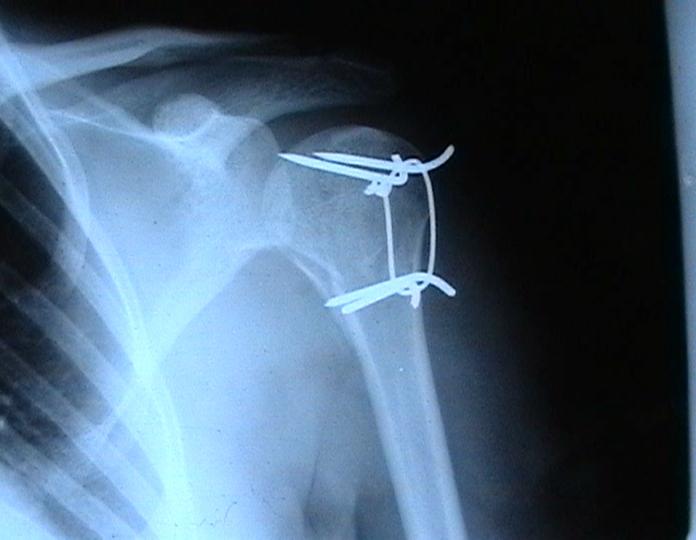

Переломовывих плеча сложная проблема и технически не уверен как для коллег, но для меня сколько я не встречался, технически сложно *вытянуть* вывихнутую головку из-под впадины. Последнее время не применяю пластины для фиксации перелома, а использую спицы и проволочную петлю (тем более часто и густо спонгиозные винты не держатся в головке прочно).

Фиксация получается достаточно стабильная, правда мои заключения основаны только на клинических наблюдениях, возможности протестировать прочность фиксации в лабораторных условиях нет. Я не автор данного типа фиксации в основе его лежит принцип напряженной фиксации (Weber tension Band fixation). Когда-то у нас использовали фиксатор проф Сеппо при переломах

шейки бедра - принцип работы аналогичен, только менее громоздкие элементы конструкции и более доступные для применения в любых условиях.

Не происходит ли миграция спиц?

Я использую обычные 2 мм спицы и пока в 8 случаях , что применял подобную фиксацию миграции не было, хотя вполне вероятна такая возможность и видимо оптимальнее использовать спицы с резьбой на конце, что должно предотвратить потенциальный риск миграции. Хотя если спица начинает пальпироваться под кожей и доставлять неудобство больному, то её легко удалить в условиях перевязочной. На мой взгляд миграция спицы мложет произойти только тогда,

когда пациент начинает активно работать рукой, к этому времени перелом уже срастется, поэтому опасности скомпрометировать стабильность фиксации уже не будет.

Почему нельзя использовать только проволоку (сформировав для этого туннели в проксимальном и дистальном фрагменте ).

Я такой же практик как и Вы, поэтому решать можно или нельзя использовать только проволочную петлю решать Вам, хотя на мой взгляд, обычная проволочная петля не создает многоплоскостной стабильности фиксации, а только лишь в плоскости проведенных отверстий в проксимальном и дистальном фрагментах и другой момент зачастую такие переломы случаются у пожилых людей с порозной костью, тогда, как понимаете, проволочная петля может легко прорезаться через кость и не о какой стабильной фиксации уже речи быть не может в то время как спицы держаться в порозной кости тем более, что при такой фиксации создается момент силы, направленный не на вытягивание спицы из кости.